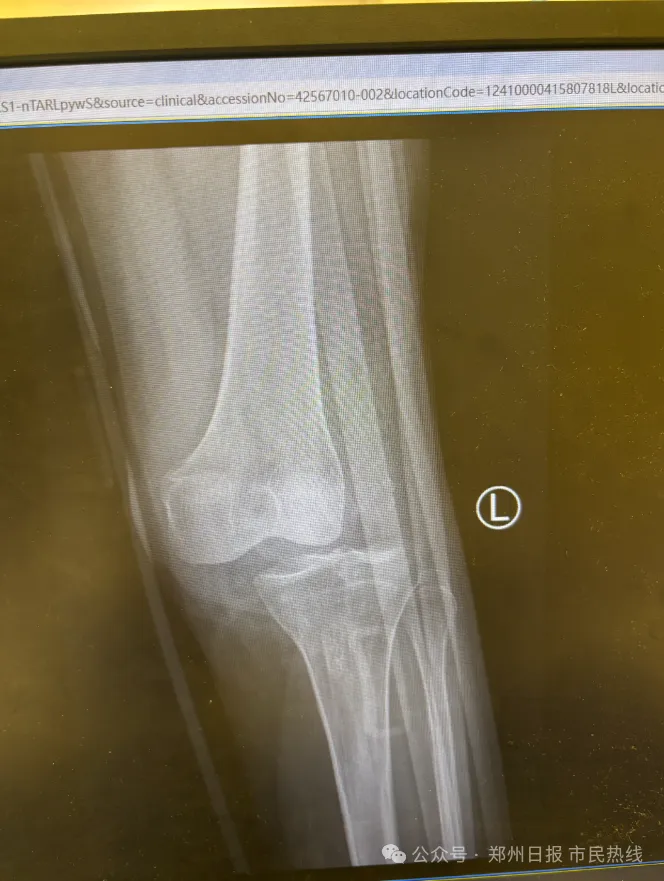

“左膝关节脱位,多处韧带断裂,伤得非常重,需多次手术治疗,且后续会影响功能。”代先生说,春节假期山地项目仍在继续运营,而景区应对家人的治疗问题时的态度也不够积极。